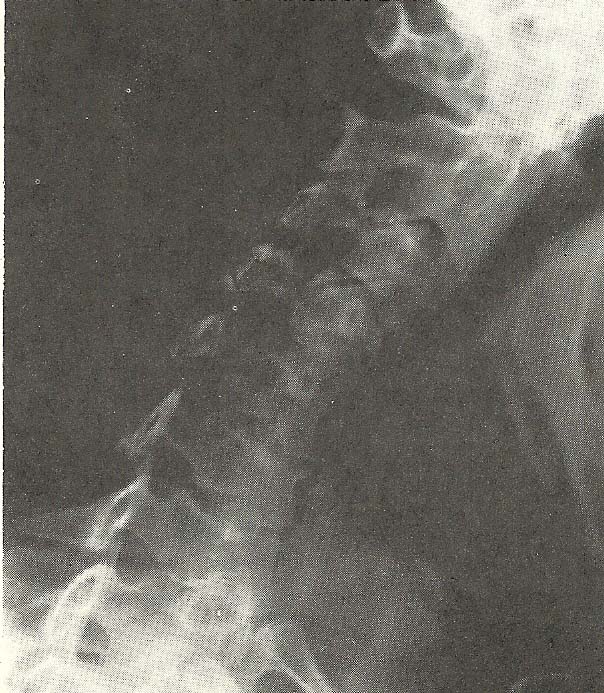

Case Illustrating Classifications B-1, C-2, C-4, A-8, and A-9

The films of this case (Figs. 6.61--6.67) show alteration of the cervical

lordosis in the neutral lateral film and lessened ability to flex the neck,

coupled with slight hypermobility during neck extension (C-4).

As the cervical curve is naturally convex toward the anterior, alteration

of this pattern usually means pathology or significant injury to the skeletal

and/or supportive structures. Note in the neutral lateral film that there is

flexion of the C3 and C4 motion units.

With neck flexion, near total fixation or hypomobility from C3 through C6

motion units (B-1) is demonstrated. The atlantoaxial and atlanto-occipital

motion units show considerably diminished ability to flex (B-1).

Extension of the neck is accomplished, even to the point of hypermobility.

All motion units extend as far as structure allows so that the posterior

arches and spinouses approximate. By comparing the three lateral films (Figs.

6.63--6.65), we have an excellent example of abnormal mobility of a spinal

section or region (C-5). Intervertebral hypomobility is present at several

levels.

This case also exhibits manifestations of other radiologically evident

subluxations. The decreased disc height at C4-C5, C5-C6, and C6-C7, due to the

evident discopathy and spondylosis, is classified as decreased interosseous

spacing (A-8). The rather marked intrusion and compromise of the neural

foramina at C4-C5, C5-C6, and C6-C7, seen on the left anterior oblique film

(Fig. 6.66), and similar alteration of the foramina at the same levels

are shown on the right anterior oblique film (Fig. 6.67), also meet the

criteria of subluxation under the classification of foraminal encroachment

(A-9).

The patient is a strong 66-year-old male who has continued to work as

manager of a solid-waste disposal plant though he had passed the age of

retirement. He was suffering from pain in the neck, which radiated to the

right shoulder. The duration of the complaint, at the time the x-ray films

were made, was 3 weeks. He had this complaint on several previous occasions

and each time had experienced an excellent remission of symptoms following

chiropractic treatment. He had not had similar pain for about 3 years prior to

the time he presented himself for chiropractic care for the current episode.

Views of the right shoulder, one of which is shown in Figure 6.68, were

essentially normal. Physical examination was largely unrevealing, except that

orthopedic testing showed grossly restricted ability to laterally bend the

neck to either side, and foraminal compression tests were positive

bilaterally.

The moderately severe degenerative disease the x-ray examination reveals

in this man's neck are chronic. The relatively short duration of the present

symptom complex suggests that his current pain is more related to neuralgia

from functional disturbance in his neck than to a chronic neuropathy. The

foraminal encroachment of sufficient magnitude and severity to suggest neural

canal stenosis.

Chiropractic adjustment and reflex techniques brought marked relief in

three treatments over a 1-week span. Two treatments the following week were

able to bring a near total remission of the pain. He continued with weekly

treatments for 2 more weeks, stating that he felt markedly better. Following

the 4th week of care, he was discharged from active treatment and advised to

return periodically as symptoms dictated. He has continued with monthly

visits, at his request, since he feels much better under such a regimen.